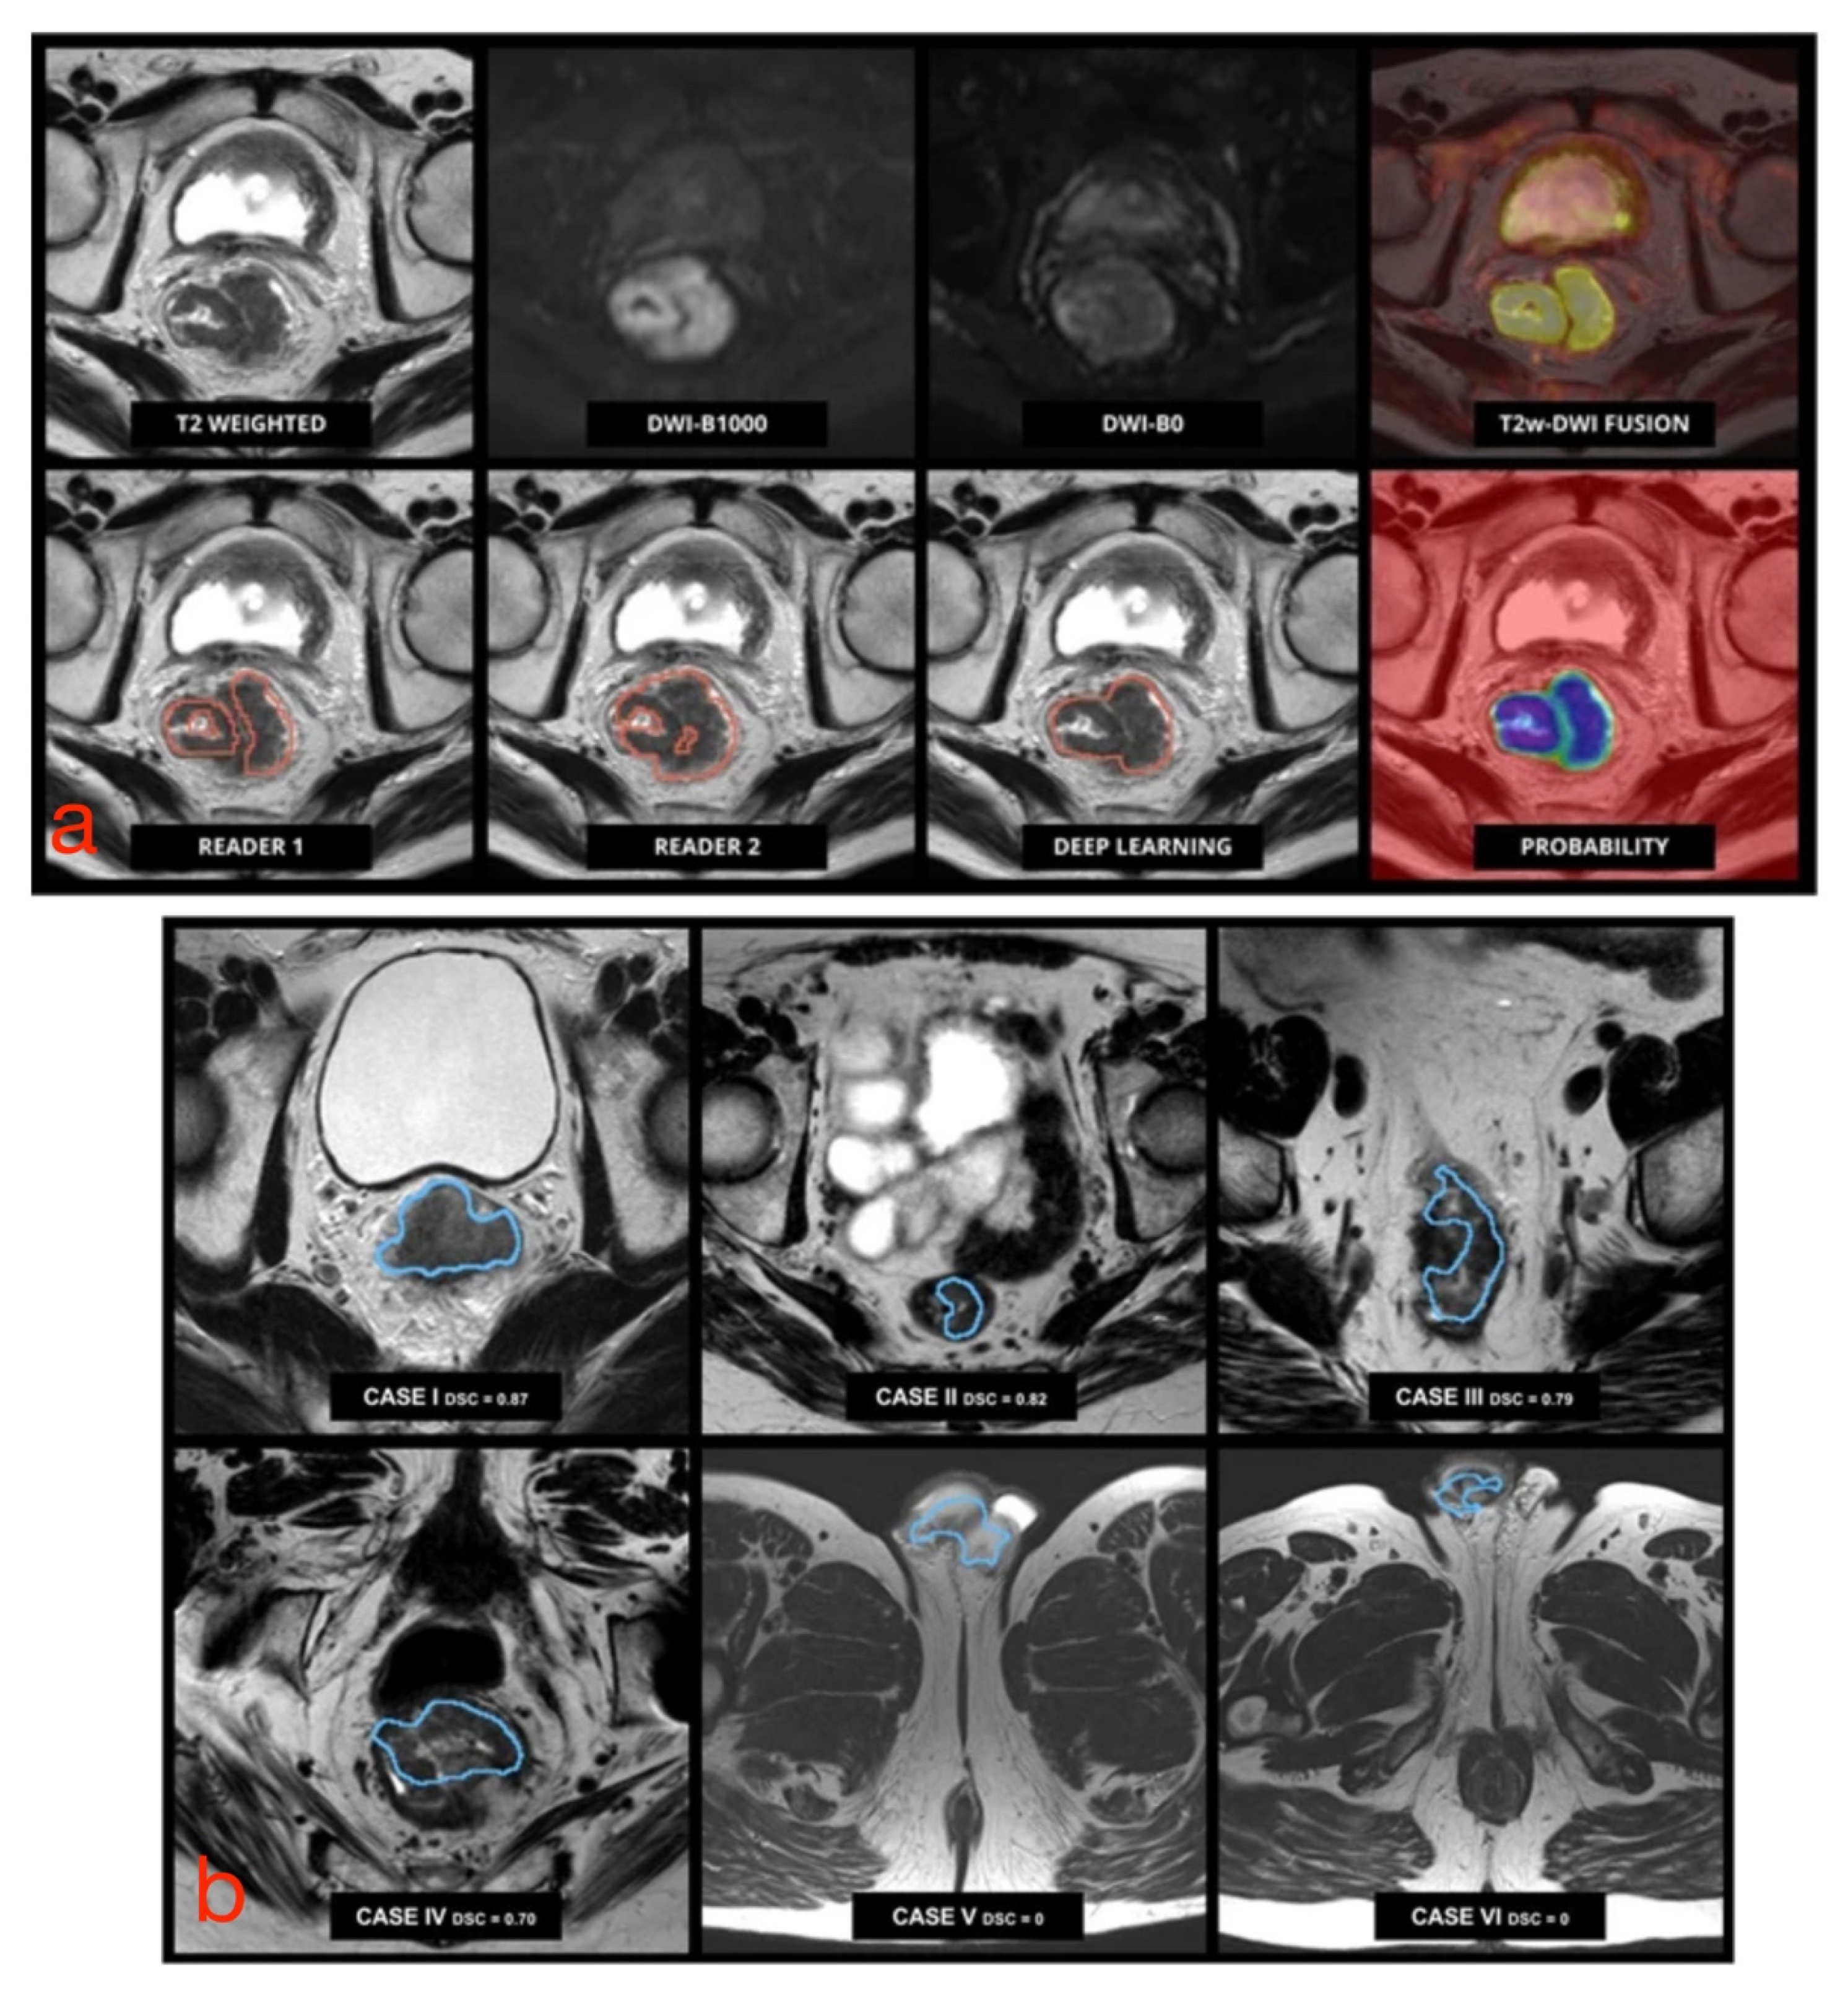

To date, there has been an ever-increasing number of studies showing systems based on neural networks for the segmentation of RC, given the greater interest in such technologies and their potential medical applications. The best results related to the application of CNNs have been illustrated by Trebeschi et al., who implemented a CNN-based system using multiparametric rectal MRI [46]. This system accepts T2-weighted and DW images (b-values equal to 0 and 1000 s/mm2) as input and is capable of classifying each voxel (3D region of the image) as neoplastic or healthy tissue (Figure 4a). The main disadvantage of this system is that its performance decreases considerably when input MR images have been acquired with a wider field of view than that of the learning dataset since portions of healthy tissue (such as testicles or subcutaneous adipose tissue) are classified as tumor tissue (Figure 4b). Huang et al. implemented a U-net, which allowed successful tumor localization on T2-weighted images [47]; however, it required a long computational time, which negated any substantial practical advantage than manual segmentation. The same authors showed the possibility of training a neural network, even using an unbalanced dataset, such as a hospital dataset in which the percentage of patients with a given disease is lower than that of healthy individuals [48]. This was possible by “weighting” the effects of pathological cases more and nonpathological cases less on the network.

Figure 4. (a) Pretreatment multiparametric rectal MRI examination in a male patient with RC. Upper row (from left to right): axial MR images from T2-weighted images, DWI b1000, DWI b0, and fusion imaging between T2-weighted and DWI b1000 images. Lower row (from left to right): tumor segmentation performed by an experienced reader used for training, an independent reader, the algorithm output, and the corresponding probability map generated by the algorithm. (b) Performance of CNN-based segmentation. The algorithm correctly identified and segmented the tumor in cases I to IV (small field of view), but it failed with a larger field of view images (V and VI), where parts of the cavernous bodies of the penis were mistakenly included in the segmentation. Adapted from [46].